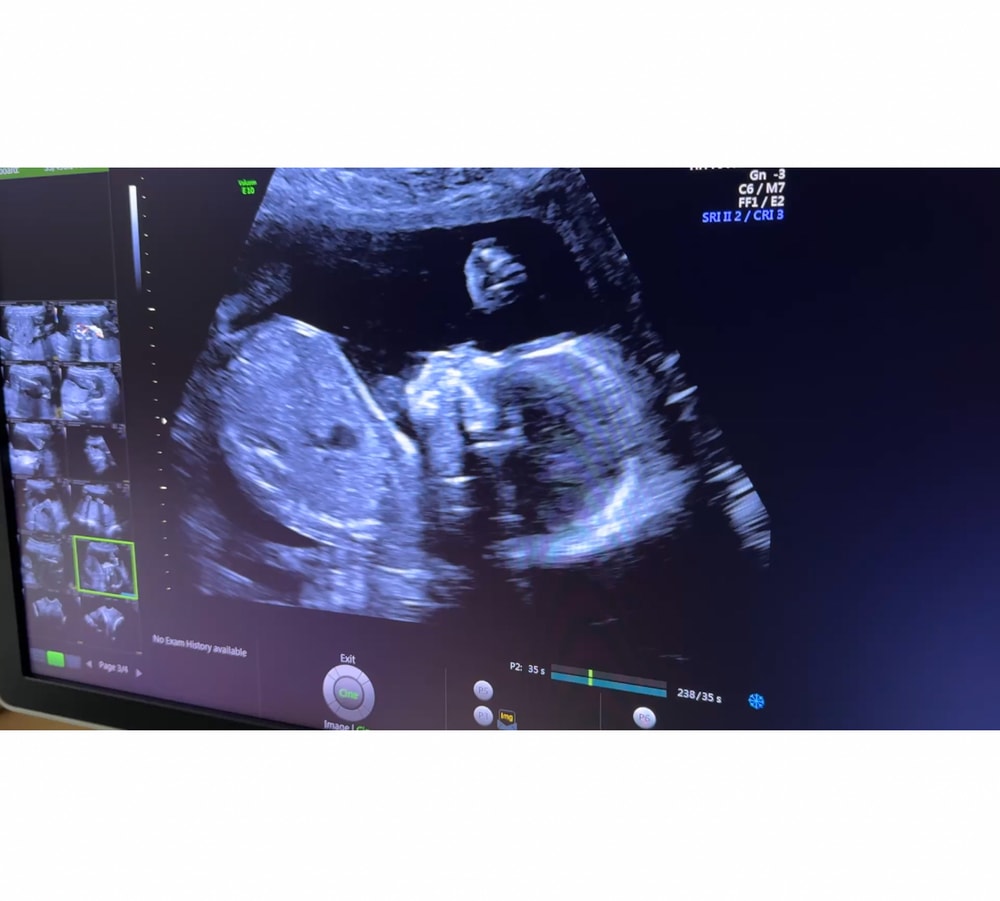

Ну вот и прошли мы третий скрининг в 35 недель. Вес чуть больше чем 2400, все в норме! Слава Богу 🙏🙏🙏 врач сказала, что никаких показаний к КС нет. Пока думаем… Еще 4-5 недель и наша малышка появится на свет.

Девочки, привет! Вчера прошли второй скрининг! Все хорошо у малыша и у меня 🙏🙏🙏 Осталось еще 18-20 неделек и наше чудо появится на свет! Прослезилась, когда увидела, как малышка машет ручкой, даже все пальчики видно (на фото тоже видно)